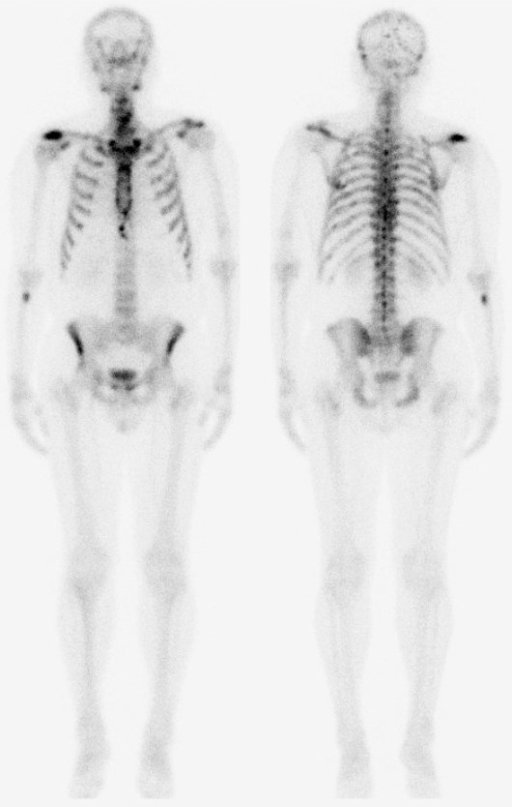

Planární scintigrafiePo aplikaci radioindikátoru dochází k jeho distribuci v určitých částech organismu, tuto distribuci pomocí zevní detekce vycházejícího záření γ zobrazujeme scintilační kamerou , v počítači vznikají digitální scintigrafické obrazy, které jednak hodnotíme vizuálně, jednak můžeme pomocí křivek matematicky analyzovat vyšetřované procesy a počítat kvantitativní parametry funkce jednotlivých orgánů.

Scintigrafie skeletu.